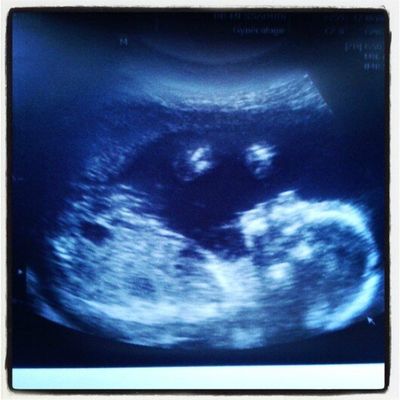

Bonjour à toutes, j'espère que la rentrée se passe bien pour vous. pour ma part, c'est repos a la maison mais à titre preventif uniquement. ma grossesse se passe bien ma petite puce grandit et commence à donner beaucoup de coups :-). j'entre dans la 19ème semaine de grossesse et voila a quoi ressemble mon petit miracle a très bientôt.